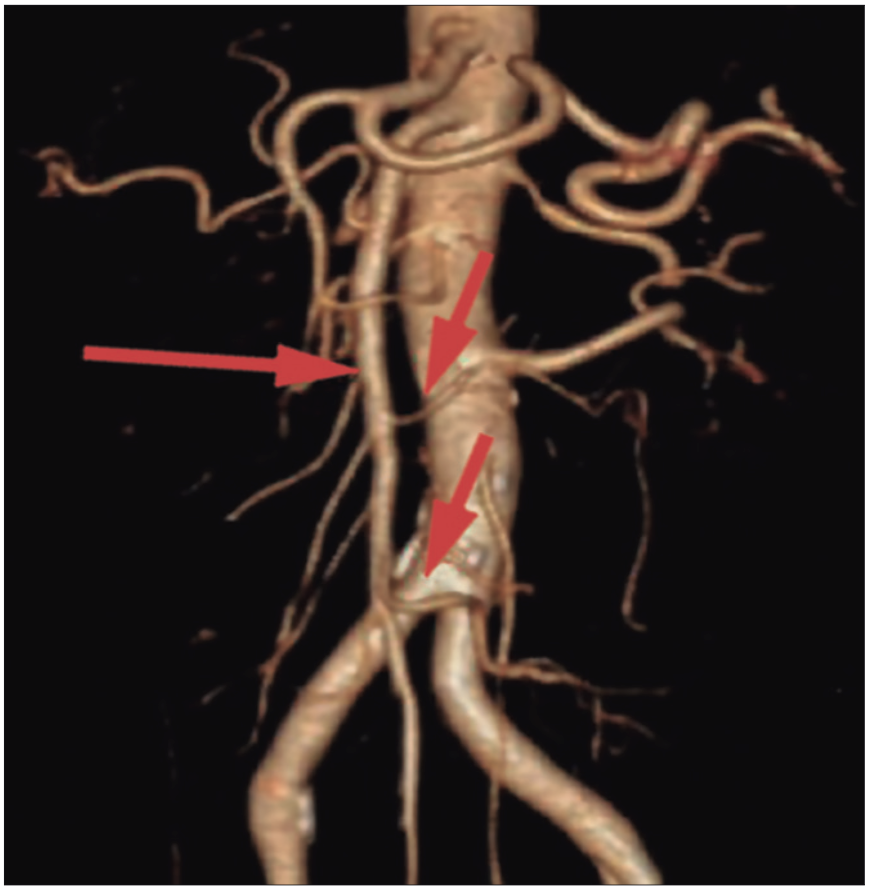

On CT angiography, the superior mesenteric artery is located to the right of the superior mesenteric vein. The right colic vessels arise directly from the superior mesenteric artery without a distinct ileocolic vessel, resembling a fetal anatomy. The left colon is supplied by the inferior mesenteric artery. Figure 2.

Figure 2. CT angiography of intestinal malrotation showing a superior mesenteric

artery with embryonic anatomy. There is a superior mesenteric axis from which small intestinal arteries

arise on the right and the right colic vessels on the left. The terminal branch irrigates the small bowel,

in contrast to the anatomy of a patient with normal rotation where the terminal branch is the ileocolic

artery. Long arrow: superior mesenteric artery. Short arrows: middle colic and ileocolic arteries